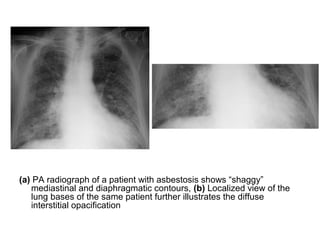

2-Interstitial Fibrosis (Asbestosis) :

-Features on chest radiographs include ground-glass

opacification, small nodular opacities, “shaggy” cardiac

silhouette, and ill-defined diaphragmatic contours, it has

been reported that 80% of patients with asbestosis have

coexistent pleural disease at chest radiography, fibrous

bands are sometimes seen to radiate inward from the

pleura

(a) PA radiograph of a patient with asbestosis shows “shaggy”

mediastinal and diaphragmatic contours, (b) Localized view of the

lung bases of the same patient further illustrates the diffuse

interstitial opacification

PA radiograph shows diffuse fine nodular and reticular opacification

with irregularity of mediastinal and diaphragmatic contours, the

costophrenic angles are blunted because of pleural thickening